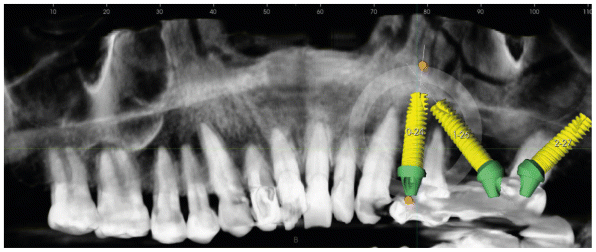

To support the proposed rehabilitation plan, a second-level examination, such as CBCT (Cone Beam Computed Tomography), was performed to verify maxillary anatomy, residual bone thickness, and height, to ensure the implants were inserted in the correct position.

Using three-dimensional CBCT images, the surgery was planned using a dedicated 3D software that virtually simulates implant placement and determines the optimal inclination and inter-implant distance. The virtual design also included the pre-visualization of the prosthetic components supporting the final restoration, such as digital abutments, as part of the virtual modeling of the immediate loading rehabilitation plan.